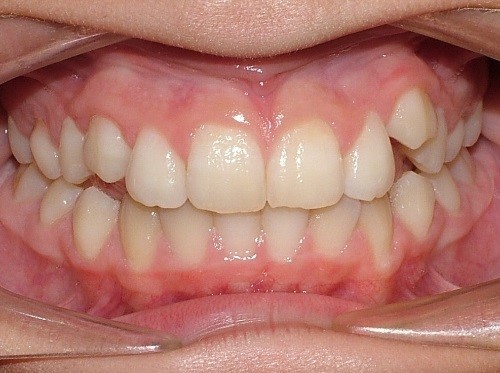

Key #2: An expander during the early mixed dentition allows the primary teeth to anchor the expansion appliance. This has significant benefits for permanent dentition that eliminate potential adverse effects, including dehiscence of the buccal bone, gingival recession, and root resorption. Expansion appliances use the strength of the roots and surrounding bone of the teeth to which they are attached. Consequently, those teeth and supporting bone carry the lateral pressure of the expansion as the suture opens. When primary teeth support the expander, the succedaneous bicuspids and canines do not bear any expansion pressure. The newly erupting teeth only benefit from the additional space development the expander has created. The acrylic bonded expander is easily constructed to adapt exclusively to the primary dentition, and has the added benefit of spreading the attachment over several teeth on each side. A banded hyrax appliance can be attached to the second primary molars and canines, or the permanent first and primary first molar. Studies have reported that using a Haas expansion appliance attached to the second primary molars and primary canines is successful and stable.

Key #4: When teeth erupt into a prepared site with adequate bone and soft tissue support, it is ideal for long-term stability and sound periodontal support. A similar protocol is followed when preparing a site with a graft for receiving an implant or grafting in an alveolar cleft site to receive the erupting canine. To prepare the space for expansion, follow the same principles for site preparation. In a crowded developing dentition, the plan to develop eruption space will decrease the risk of ectopic eruption with a compromised gingival attachment